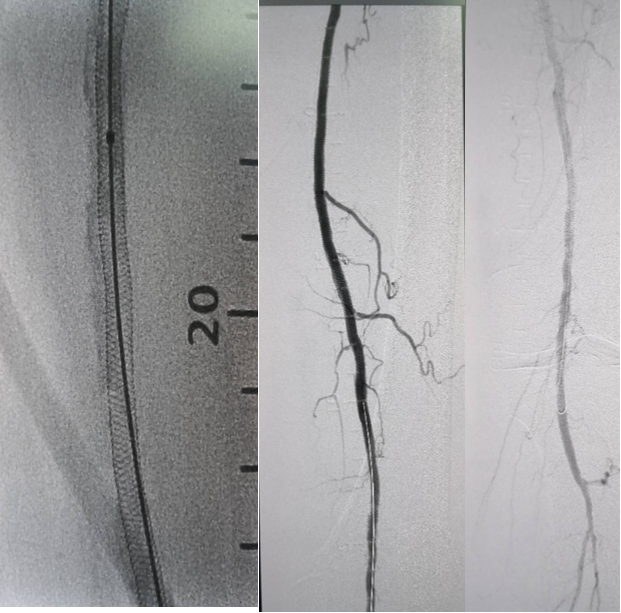

双导丝球囊(如VascuTrak):临床病例和单中心统计显示,其在低压扩张下能有效处理弹性回缩和限制性夹层,减少补救性支架的使用。

图:普通球囊管腔准备,弹性回缩明显,加用双导丝球囊

图:双导丝球囊低压扩张,后置入支架,术后造影血流满意